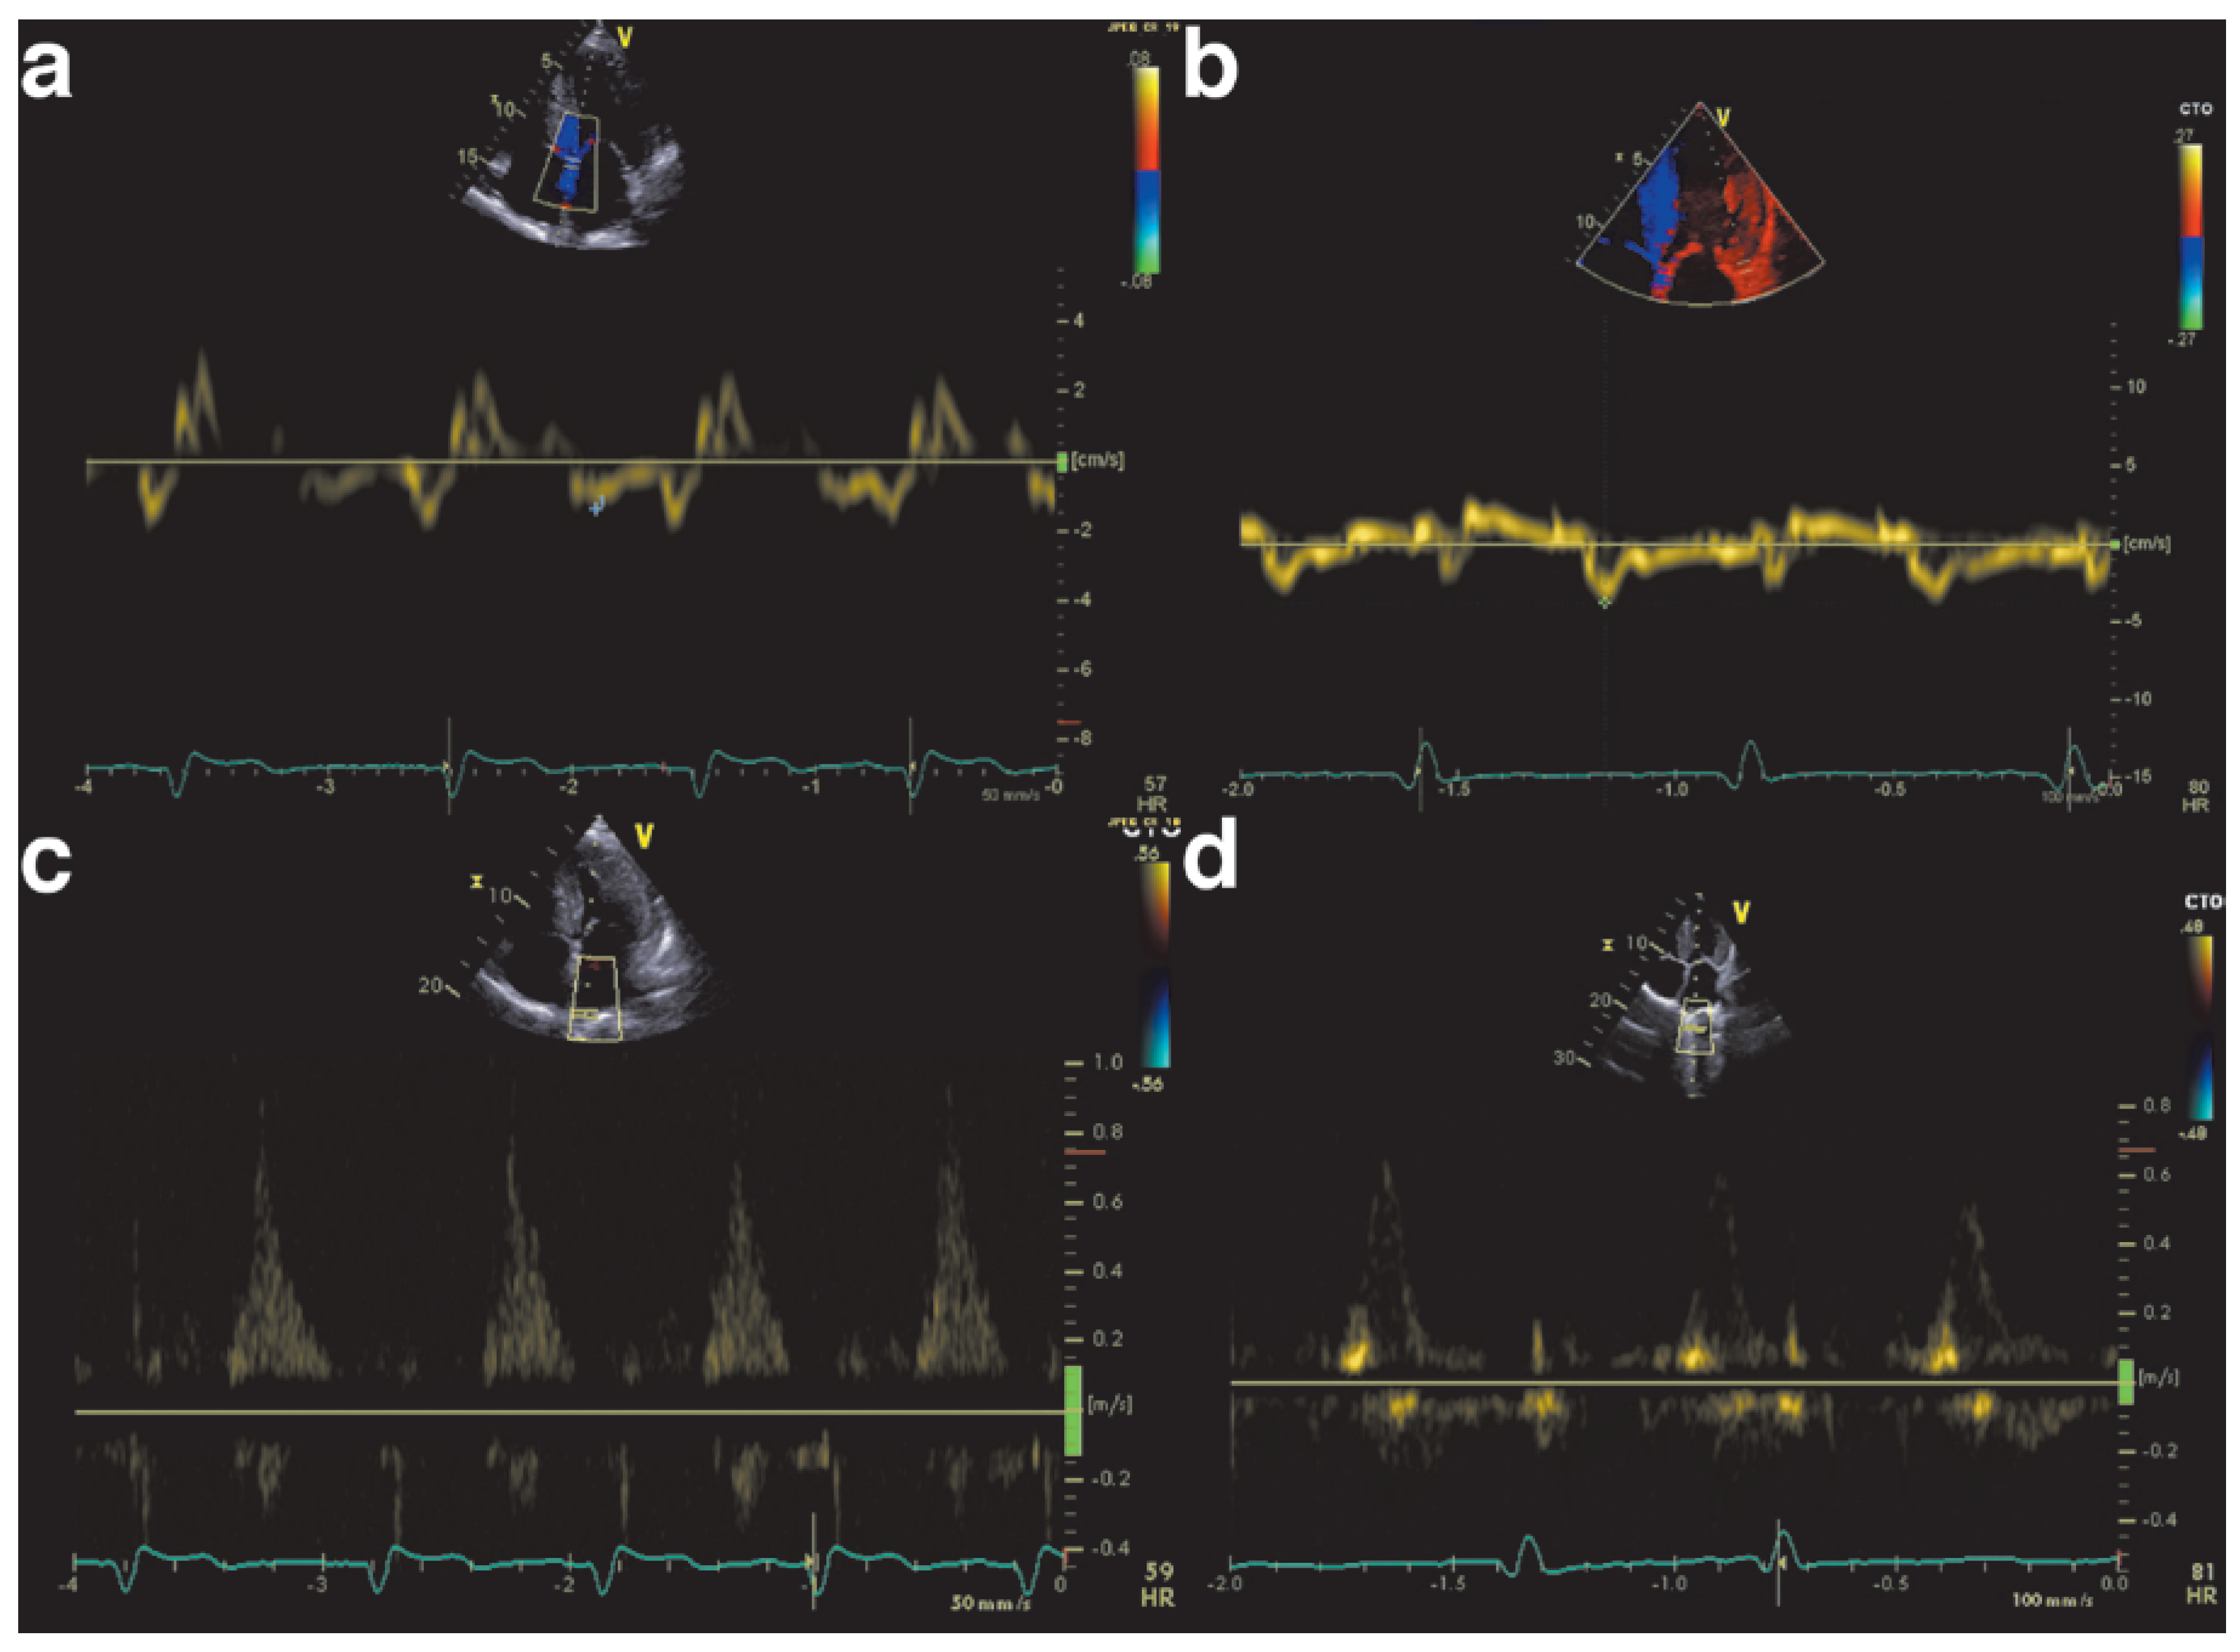

How do we diagnose cardiac amyloidosis?